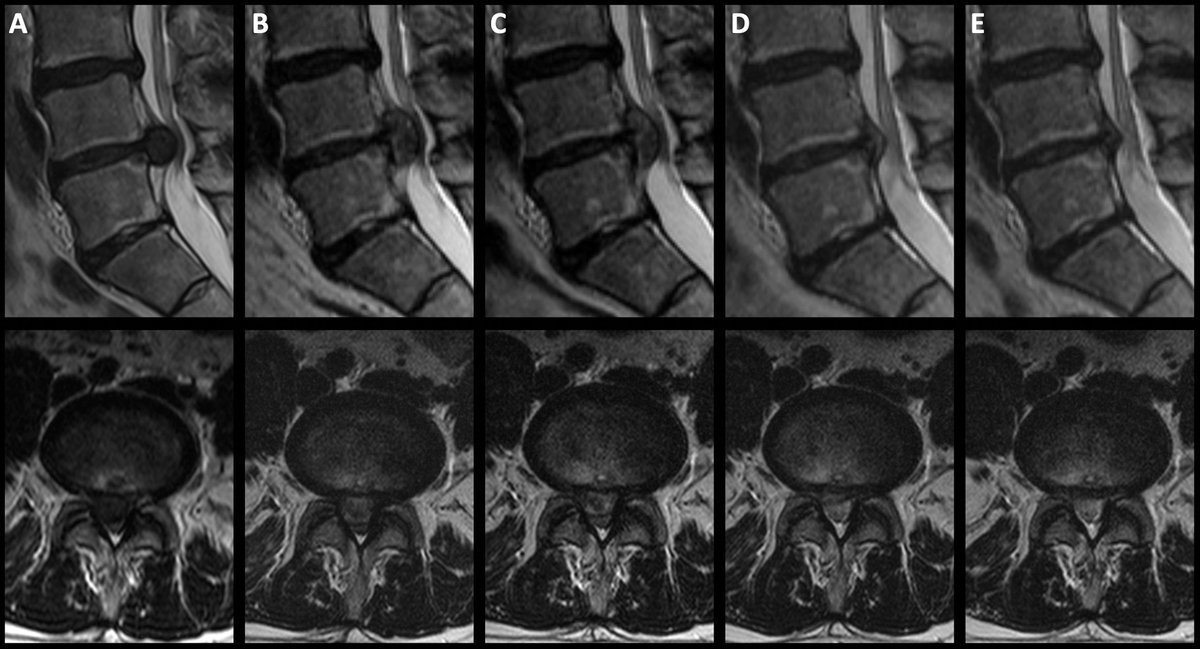

"Resorption of Lumbar Disk Herniation" https://t.co/S39eXYQv8a